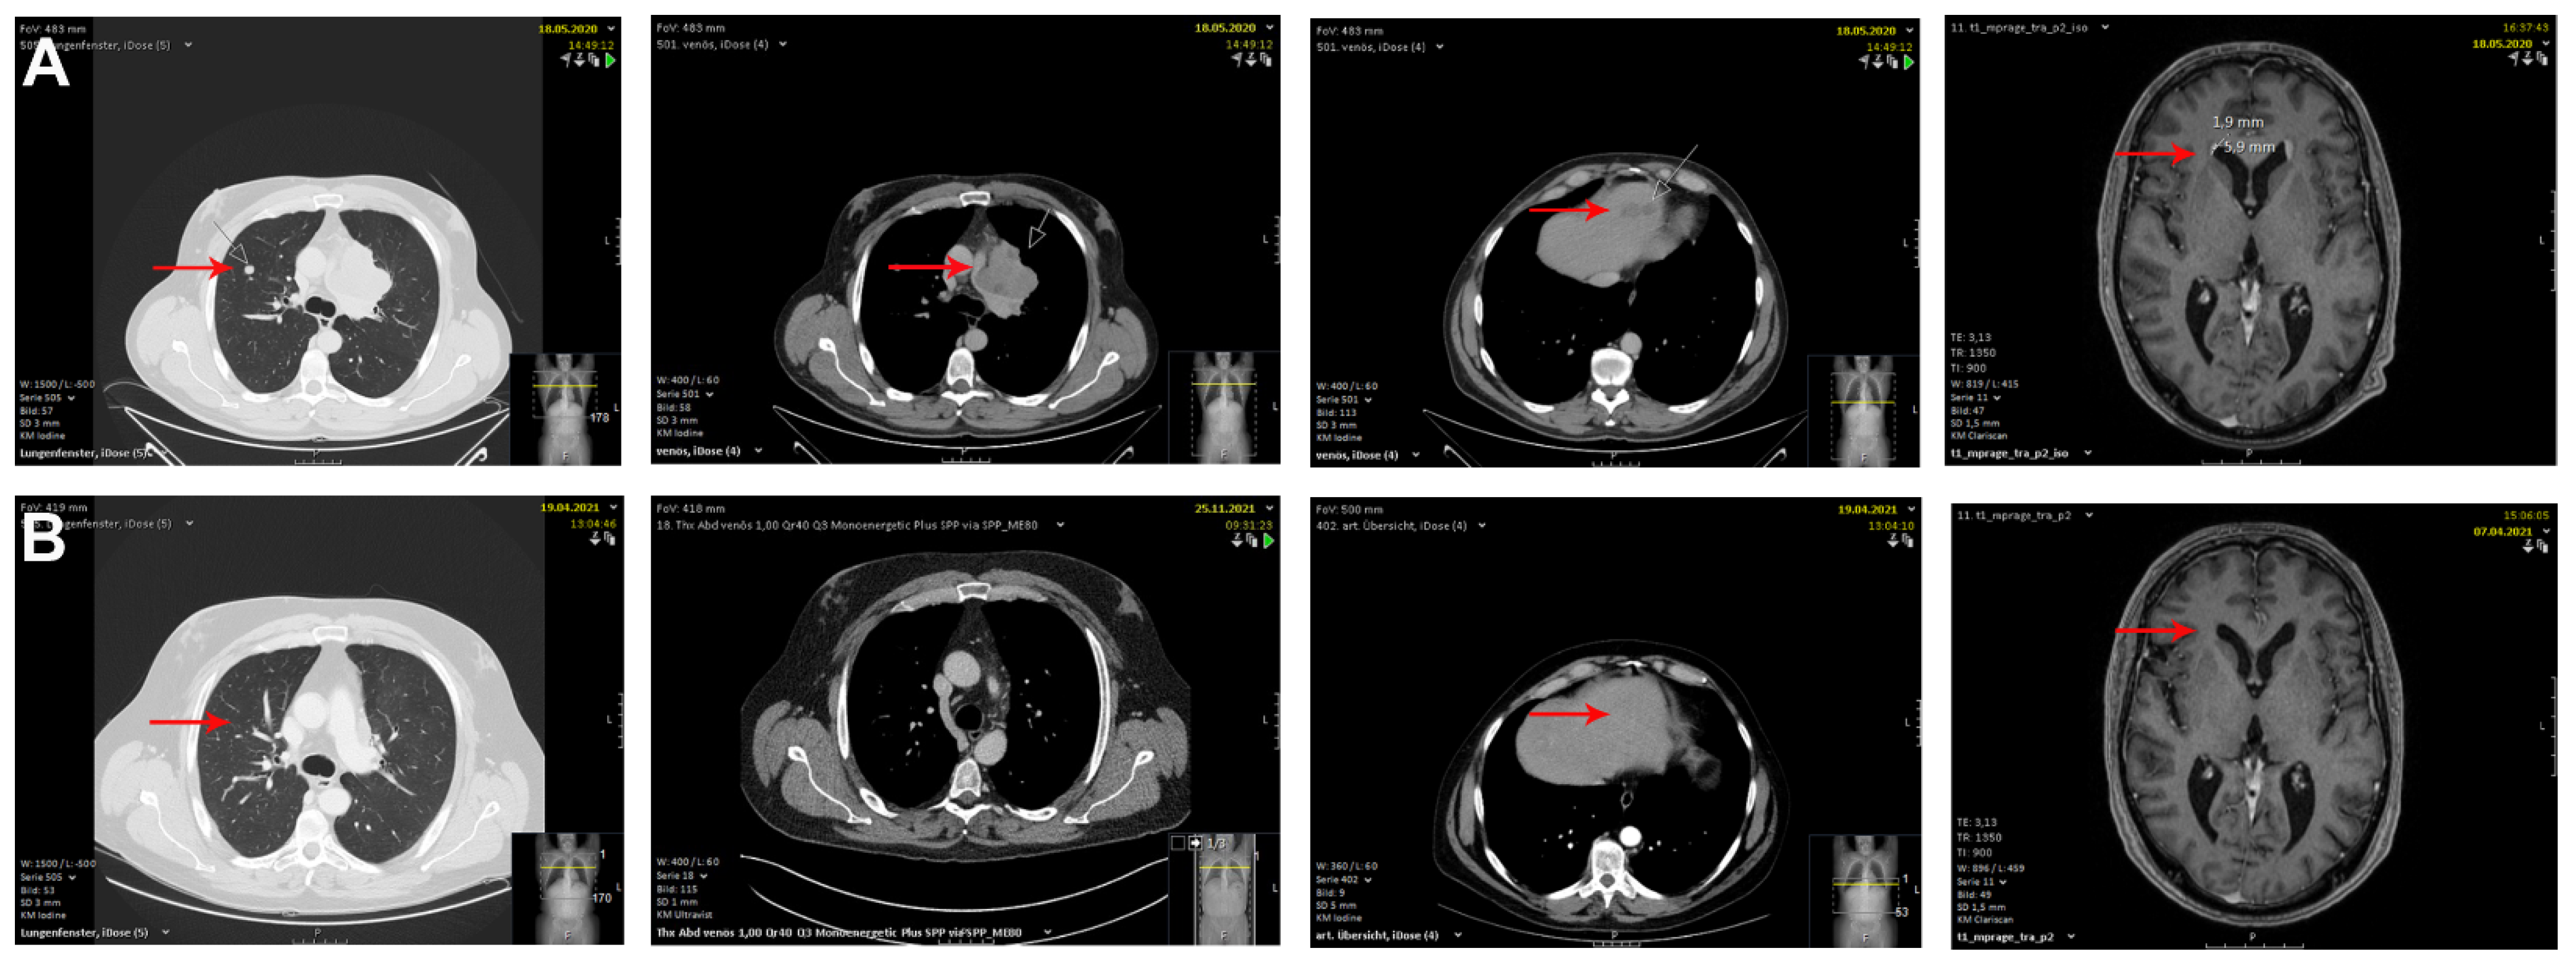

2. Case Description

| Haist et al. | unknown and upper back | 48 years and 53 years | IV | Ipilimumab + Nivolumab | After 2 and 3 cycles of cICB | complete response | hypothyroidism, vitiligo, hepatitis and colitis |